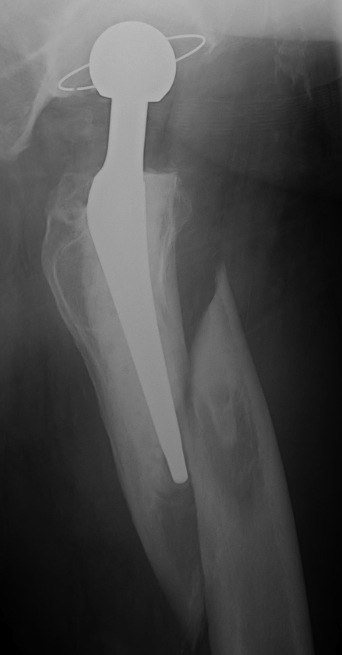

Long stem cemented revision